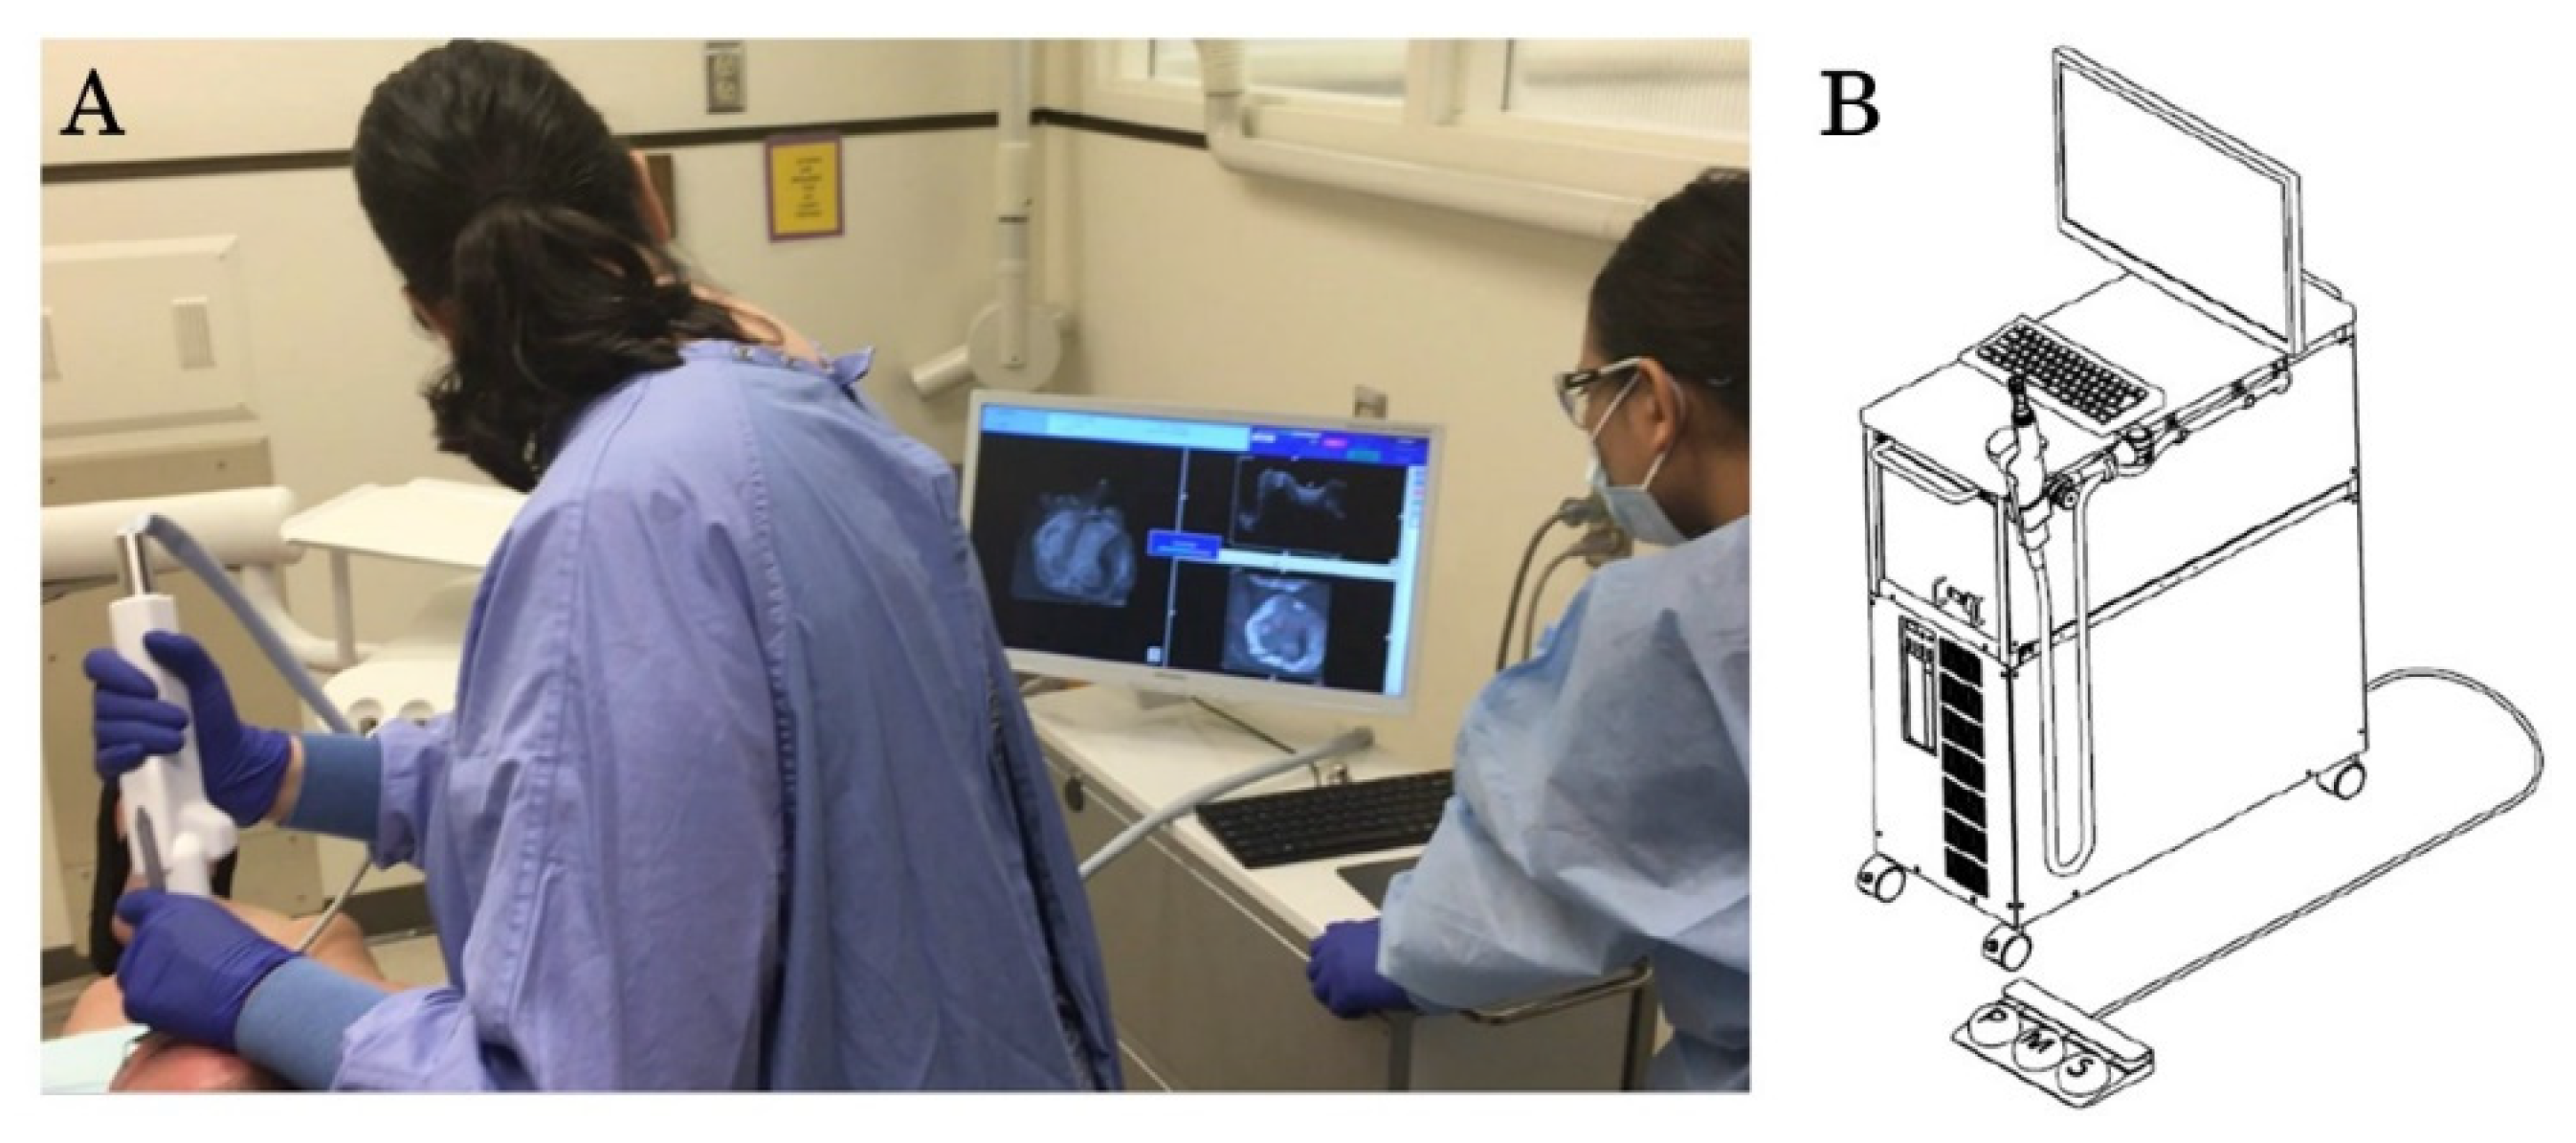

2.2. OCT Imaging Process